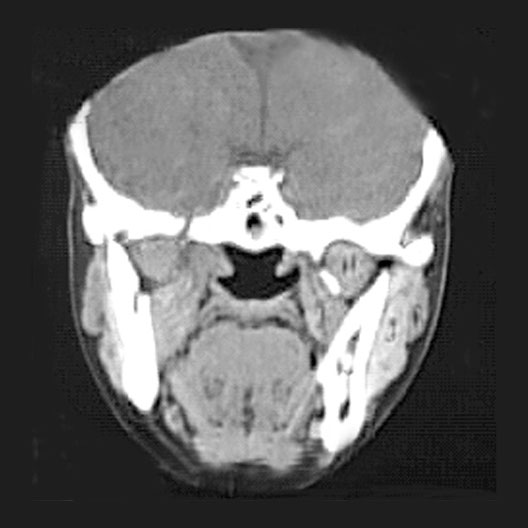

Head CT

Roll mouse over image to display labels.

1. Mylohyoid muscle

2. Genioglossus muscle

3. Digastric muscle